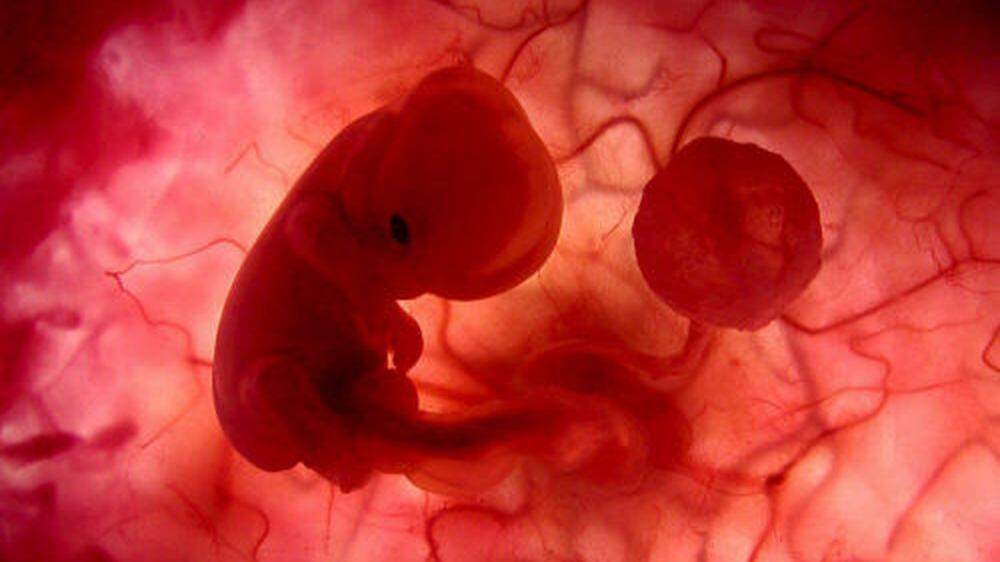

Nach einer Operation ist ein Baby in den USA nach Medienberichten "zum zweiten Mal geboren worden". Mediziner hatten die kleine LynLee einem "CNN"-Bericht zufolge in Houston (Texas) nach fast 24 Wochen Schwangerschaft aus der Gebärmutter ihrer Mutter geholt, einen Tumor am Steißbein entfernt und den Fötus zurückverpflanzt. Zwölf Wochen später kam das Mädchen gesund per Kaiserschnitt zur Welt.

Ohne Operation keine Überlebenschance

"Das ist etwas ganz Ungewöhnliches", sagte Christof Sohn, Ärztlicher Direktor der Universitätsfrauenklinik in Heidelberg, am Freitag. Der Tumor war dem Bericht zufolge nach 16 Wochen Schwangerschaft diagnostiziert worden. Wenige Wochen später war klar, dass LynLee ohne Operation keine Überlebenschance haben würde. In einem mehr als fünfstündigen Eingriff retteten die Mediziner das Baby.